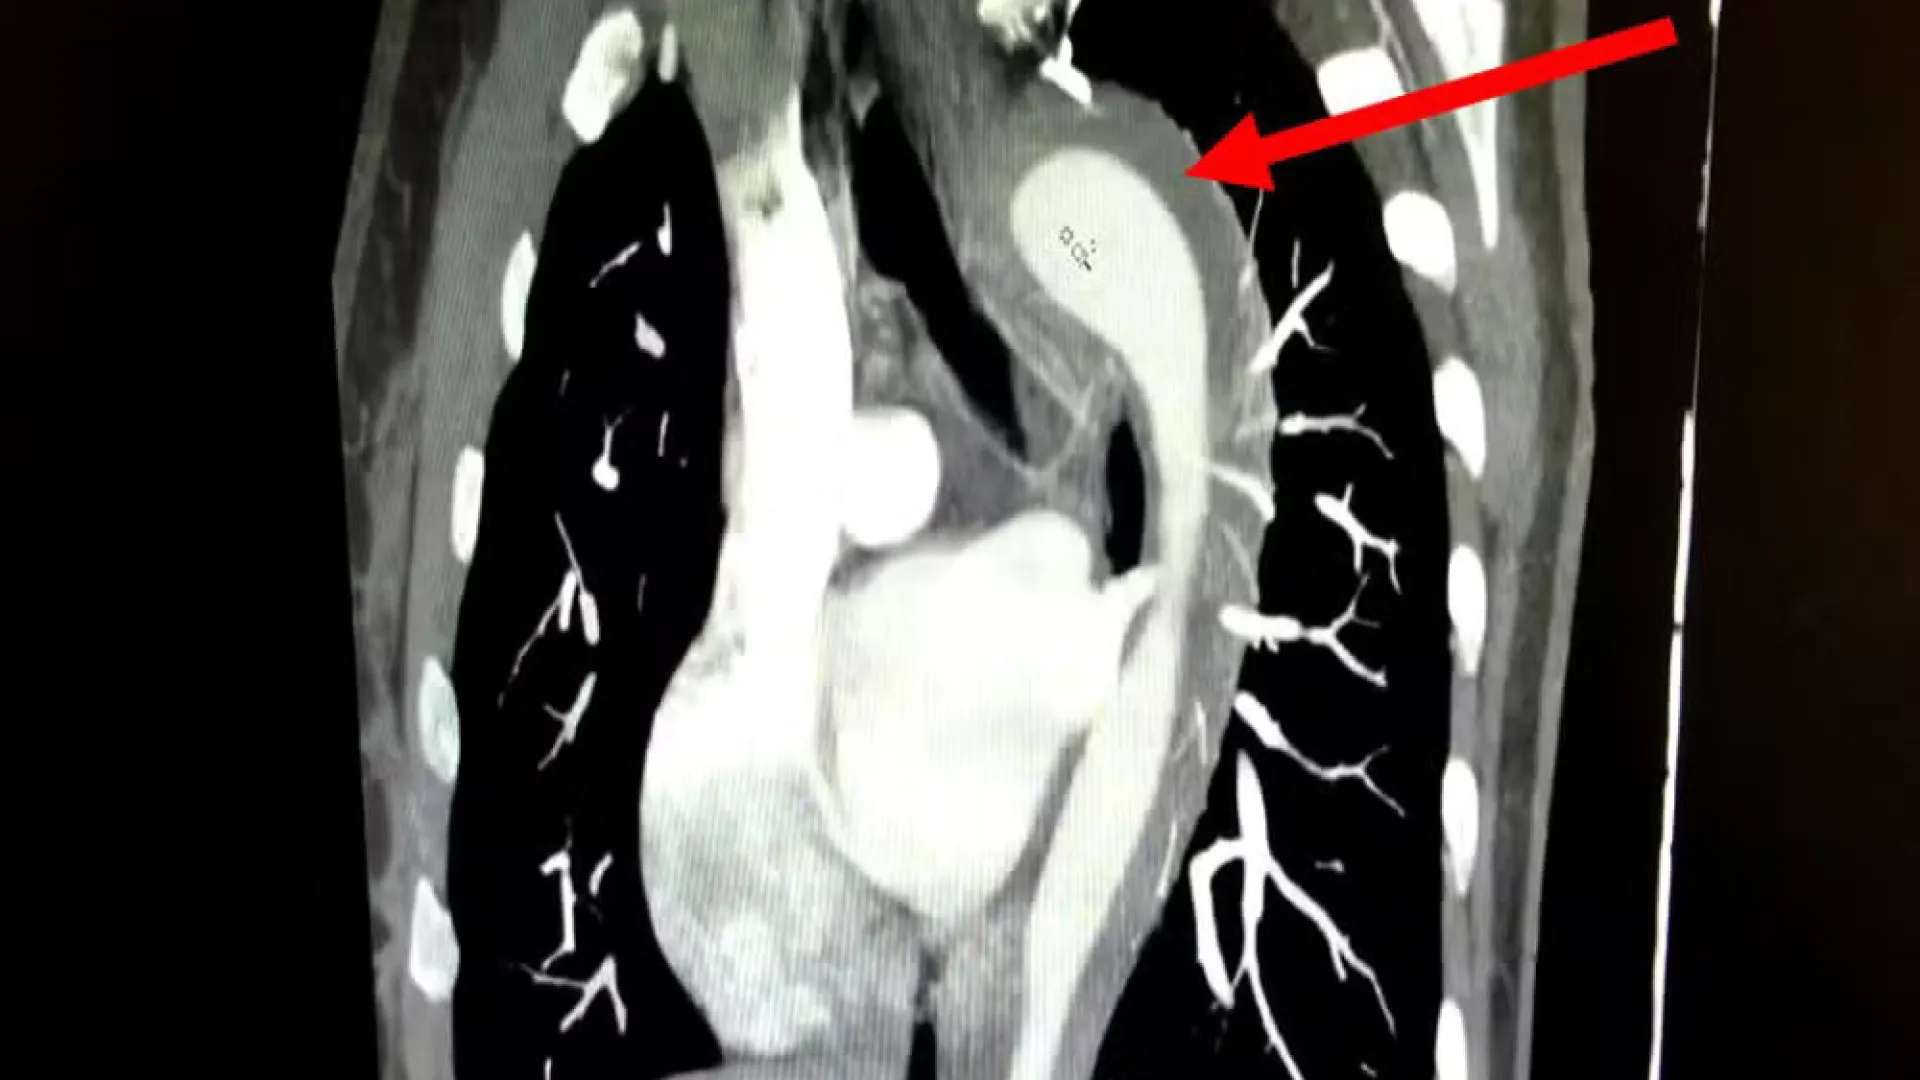

Mulher de 45 anos rompe aorta durante orgasmo e passa por cirurgia

Um caso raro e de alto risco envolvendo a ruptura da aorta foi relatado pelo American Journal of Case Reports. A paciente, uma mulher de 45 anos, d…